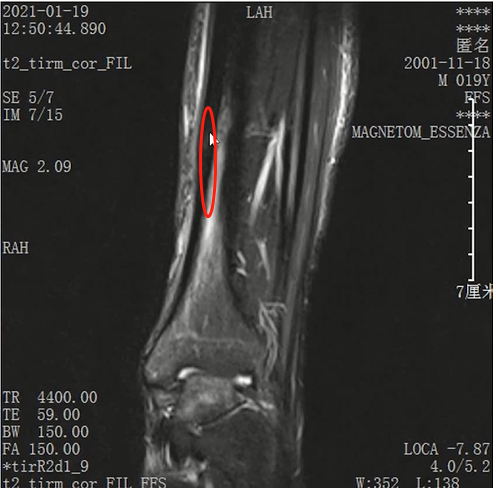

Lisfranc损伤在多发伤病人中常常容易漏诊,大约为 20-30%的漏诊率!